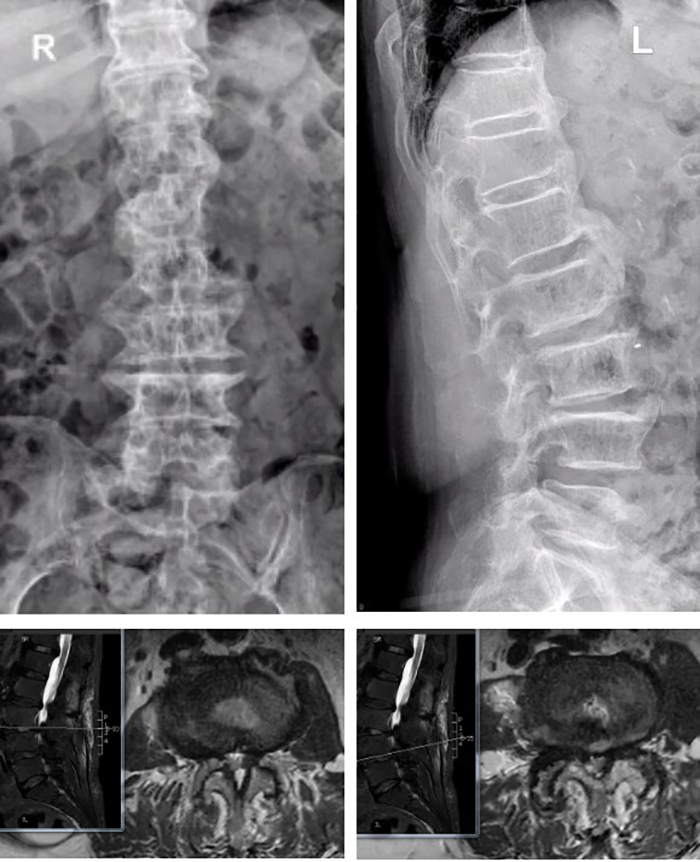

陈瑞松副主任医师接诊后,经过详细询问病史、全面查体,并结合影像学检查,诊断为腰椎椎管重度狭窄症。考虑到张阿婆年事已高,有高血压、冠心病、糖尿病、骨质疏松病史,陈瑞松副主任医师建议其采用微创手术治疗。据介绍,相较于常规开放手术,脊柱微创手术有创伤小、出血少、恢复快等优点,是高龄患者的福音。

术前影像